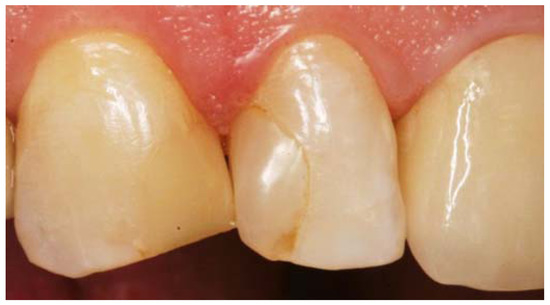

Figure 1. Conformance of visual assessment with optical coherence tomography. (a) Extracted human premolar with a carious lesion (L) of International Caries Detection and Assessment System (ICDAS II) Code 1. The lesion is visually detectable only after drying. Marks define the region of interest (ROI); (b) In the cross-sectional image of the ROI, generated using spectral domain OCT, bright shadowed spots reveal the lesion area is limited to the first half of the enamel (E); (c) After sectioning, demineralization can be imaged using dark-field light microscopy (DFLM) corresponding to the lesion details in the OCT image. D: dentin, EDJ: enamel-dentin junction.

Today the big challenge in caries diagnosis is the detection of very early stages of demineralization, especially in enamel [12,39]. Effective caries management presupposes that these early lesions (represented by porous areas very different in extension) can be reliably recorded. On smooth tooth surfaces, beginning demineralizations can be detected visually as white spot lesions on dried enamel surfaces (ICDAS II Code 1, Figure 1) [3,40], which are a common complication during treatment with fixed orthodontic appliances [41]. At this stage, the subsurface enamel porosity can be stopped or reversed using appropriate non- or minimally invasive therapies and biofilm control [8]. White spot lesions appear whitish as the incident light is backscattered off porous regions to a considerable extent [29,39]. OCT makes use of the same phenomenon. In contrast to the clinical detection solely at the surface, OCT can image structures up to a depth of 2.5 mm and might therefore be a useful supplement to the visual-tactile assessment of tooth surfaces (ICDAS II) and radiography. More reliable differentiation between the really early lesion signs (ICDAS II Codes 0–2) might become possible, irrespective of existing color changes or surface moisture (Figure 1 and Figure 2). Unlike other diagnostic methods, cross-sectional OCT images can present the axial and lateral extension of different demineralized zones (Figure 5).

In vitro studies showed an adequate to strong agreement, when SS- or SD-OCT were compared to histology [29,42,43], confocal microscopy, X-ray microtomography, or transverse microradiography and a diagnostic superiority compared to bitewing radiography [44] (Figure 1, Figure 2, Figure 5, Figure 6, Figure 7, Figure 8, Figure 9, Figure 10, Figure 11 and Figure 14).